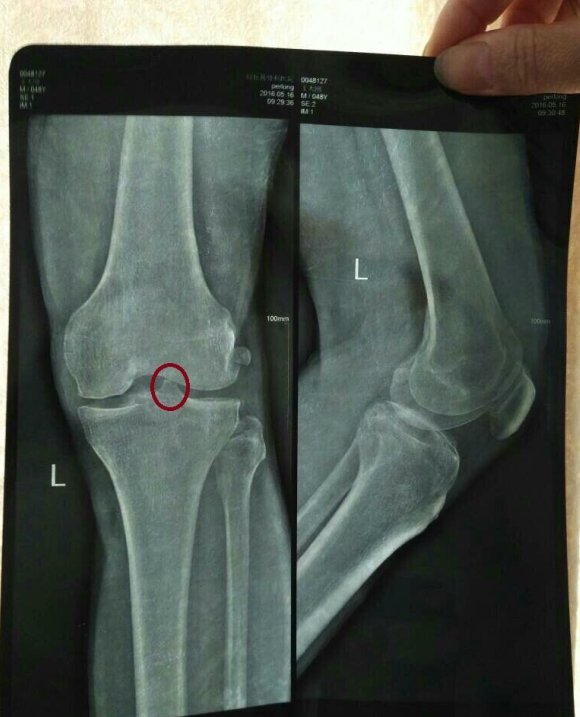

我先说说我家的情况吧,老家江西的,我爸今年45岁,6年膝盖骨质增生,基本上下不了床,每次下雨潮湿,冷点的天气就痛得牙齿直打哆嗦,我妈妈每次给他穿裤子的时候都叫的嗷嗷叫,过后还生气锤床板,试过针灸,推拿,热敷,还有很多很多其他的偏方,当时好了点,但不治根!